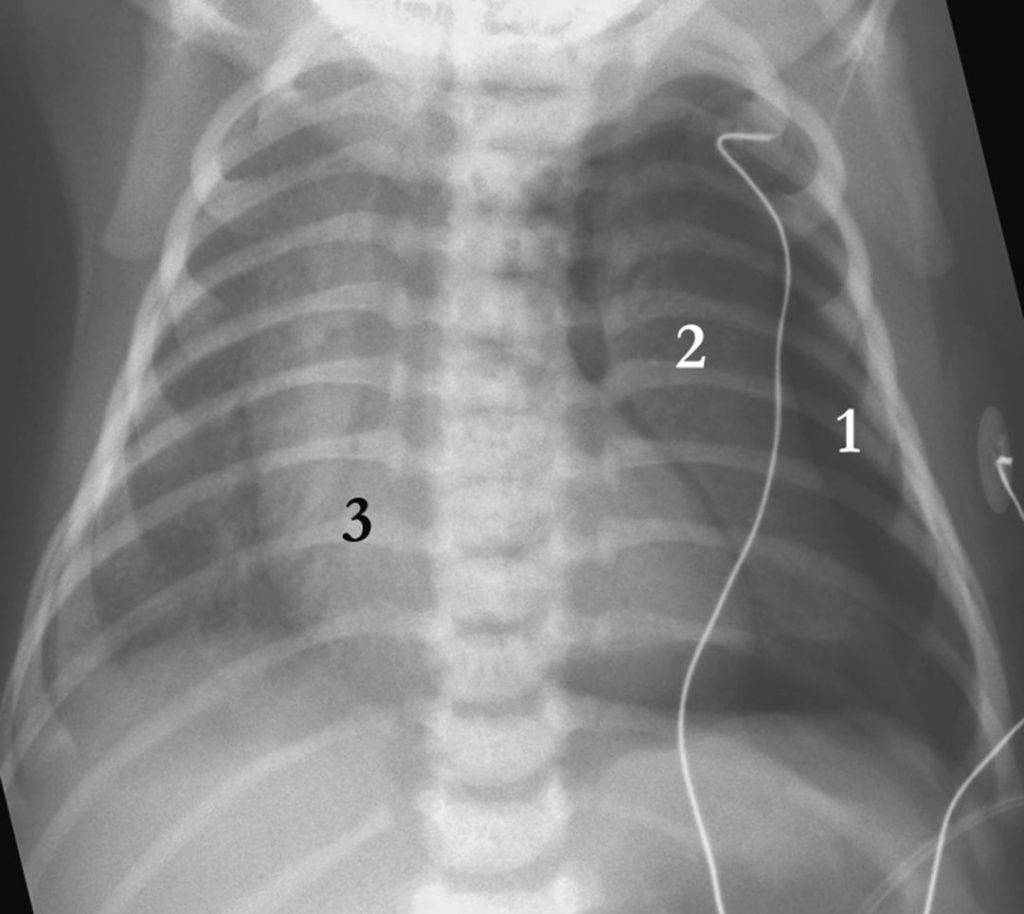

Classiquement, le pneumothorax se traduit par une hyperclarté (image aérique) périphérique située entre la paroi thoracique et le poumon et entre le poumon et le médiastin, entraînant en fonction du volume une rétraction du poumon homolatéral au niveau du hile et une déviation médiastinale controlatérale (figure 124.2). La sémiologie du pneumothorax chez le nouveau-né peut différer de celui du grand enfant ou de l’adulte car les clichés sont réalisés en position couchée et que le poumon du nouveau-né se collabe peu ; l’air se collecte alors sous la paroi thoracique antérieure et fait basculer le poumon en dehors ou en arrière en fonction du volume de l’épanchement. Une seconde différence technique est la projection antéropostérieure des rayons X, entraînant un effet d’agrandissement de la silhouette cardiomédiastinale, donnant l’impression d’une cardiomégalie.

Fig. 124.2 Radiographie thoracique de face, couché : pneumothorax gauche.

Collection aérique périphérique (1), poumon gauche rétracté (2), déviation du médiastin à droite (3).

Source : CERF, CNEBMN, 2022.